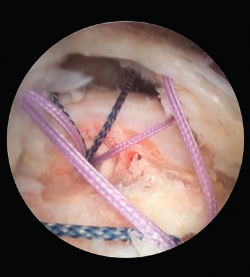

Las roturas que sí se deben reparar son las que presentan un grado de artrosis moderada(9) y aquellas con una delaminación del margen de la rotura (Figura 2). Últimamente, también se está considerando que los pacientes con factores específicos de mal pronóstico (tabaquismo, obesidad, edad, pobre calidad del tejido tendinoso…) son susceptibles de realizar una reparación de la rotura del manguito rotador, ya que no se ha demostrado suficiente evidencia en cuanto a que sean factores determinantes en el resultado funcional final(10). Igualmente, se ha demostrado que factores como la mejora del dolor pueden ser más importantes en cuanto a la buena evolución de una reparación del manguito rotador, independientemente de los factores específicos clásicos(11).

Figura 2. Rotura masiva delaminada de supraespinoso e infraespinoso.